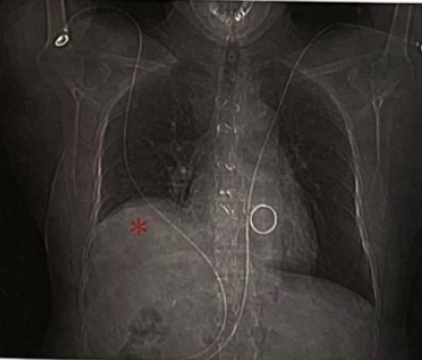

患者行胸部CT(图3)显示右肺下叶节段性膨胀不全,未见气胸表现,同时可见双侧胸腔少量积液,心影增大不明显,暂排除肺部感染、气胸、心力衰竭疾病,X线胸片(图4)提示右侧膈肌上抬,透视检查可见右侧膈肌抬高,运动幅度明显减弱(图5)。常见引起膈肌抬高的常见原因有:①肝脏占位、脓肿;②肺不张引起肺容积缩小;③膈肌麻痹。结合此患者房颤消融史,考虑可能为房颤射频消融术引起了膈神经损伤,然后出现了膈肌麻痹。

(5).png)

我院房颤导管消融术在全身麻醉下进行,在消融上腔静脉时会提前进行膈神经起搏,寻找膈神经的位置并在三位解剖图上做好标记,但由于射频消融能量存在延迟损伤的效果,在术后仍有可能出现迟发的膈神经损伤。此患者术后出现喘气的症状,术后复查X线胸片可见右侧膈肌明显抬高,考虑为膈神经损伤引起的膈肌麻痹,患者平卧位时膈肌抬高更明显,会加重喘气的症状,站立位时膈肌下移,喘气症状可有缓解。